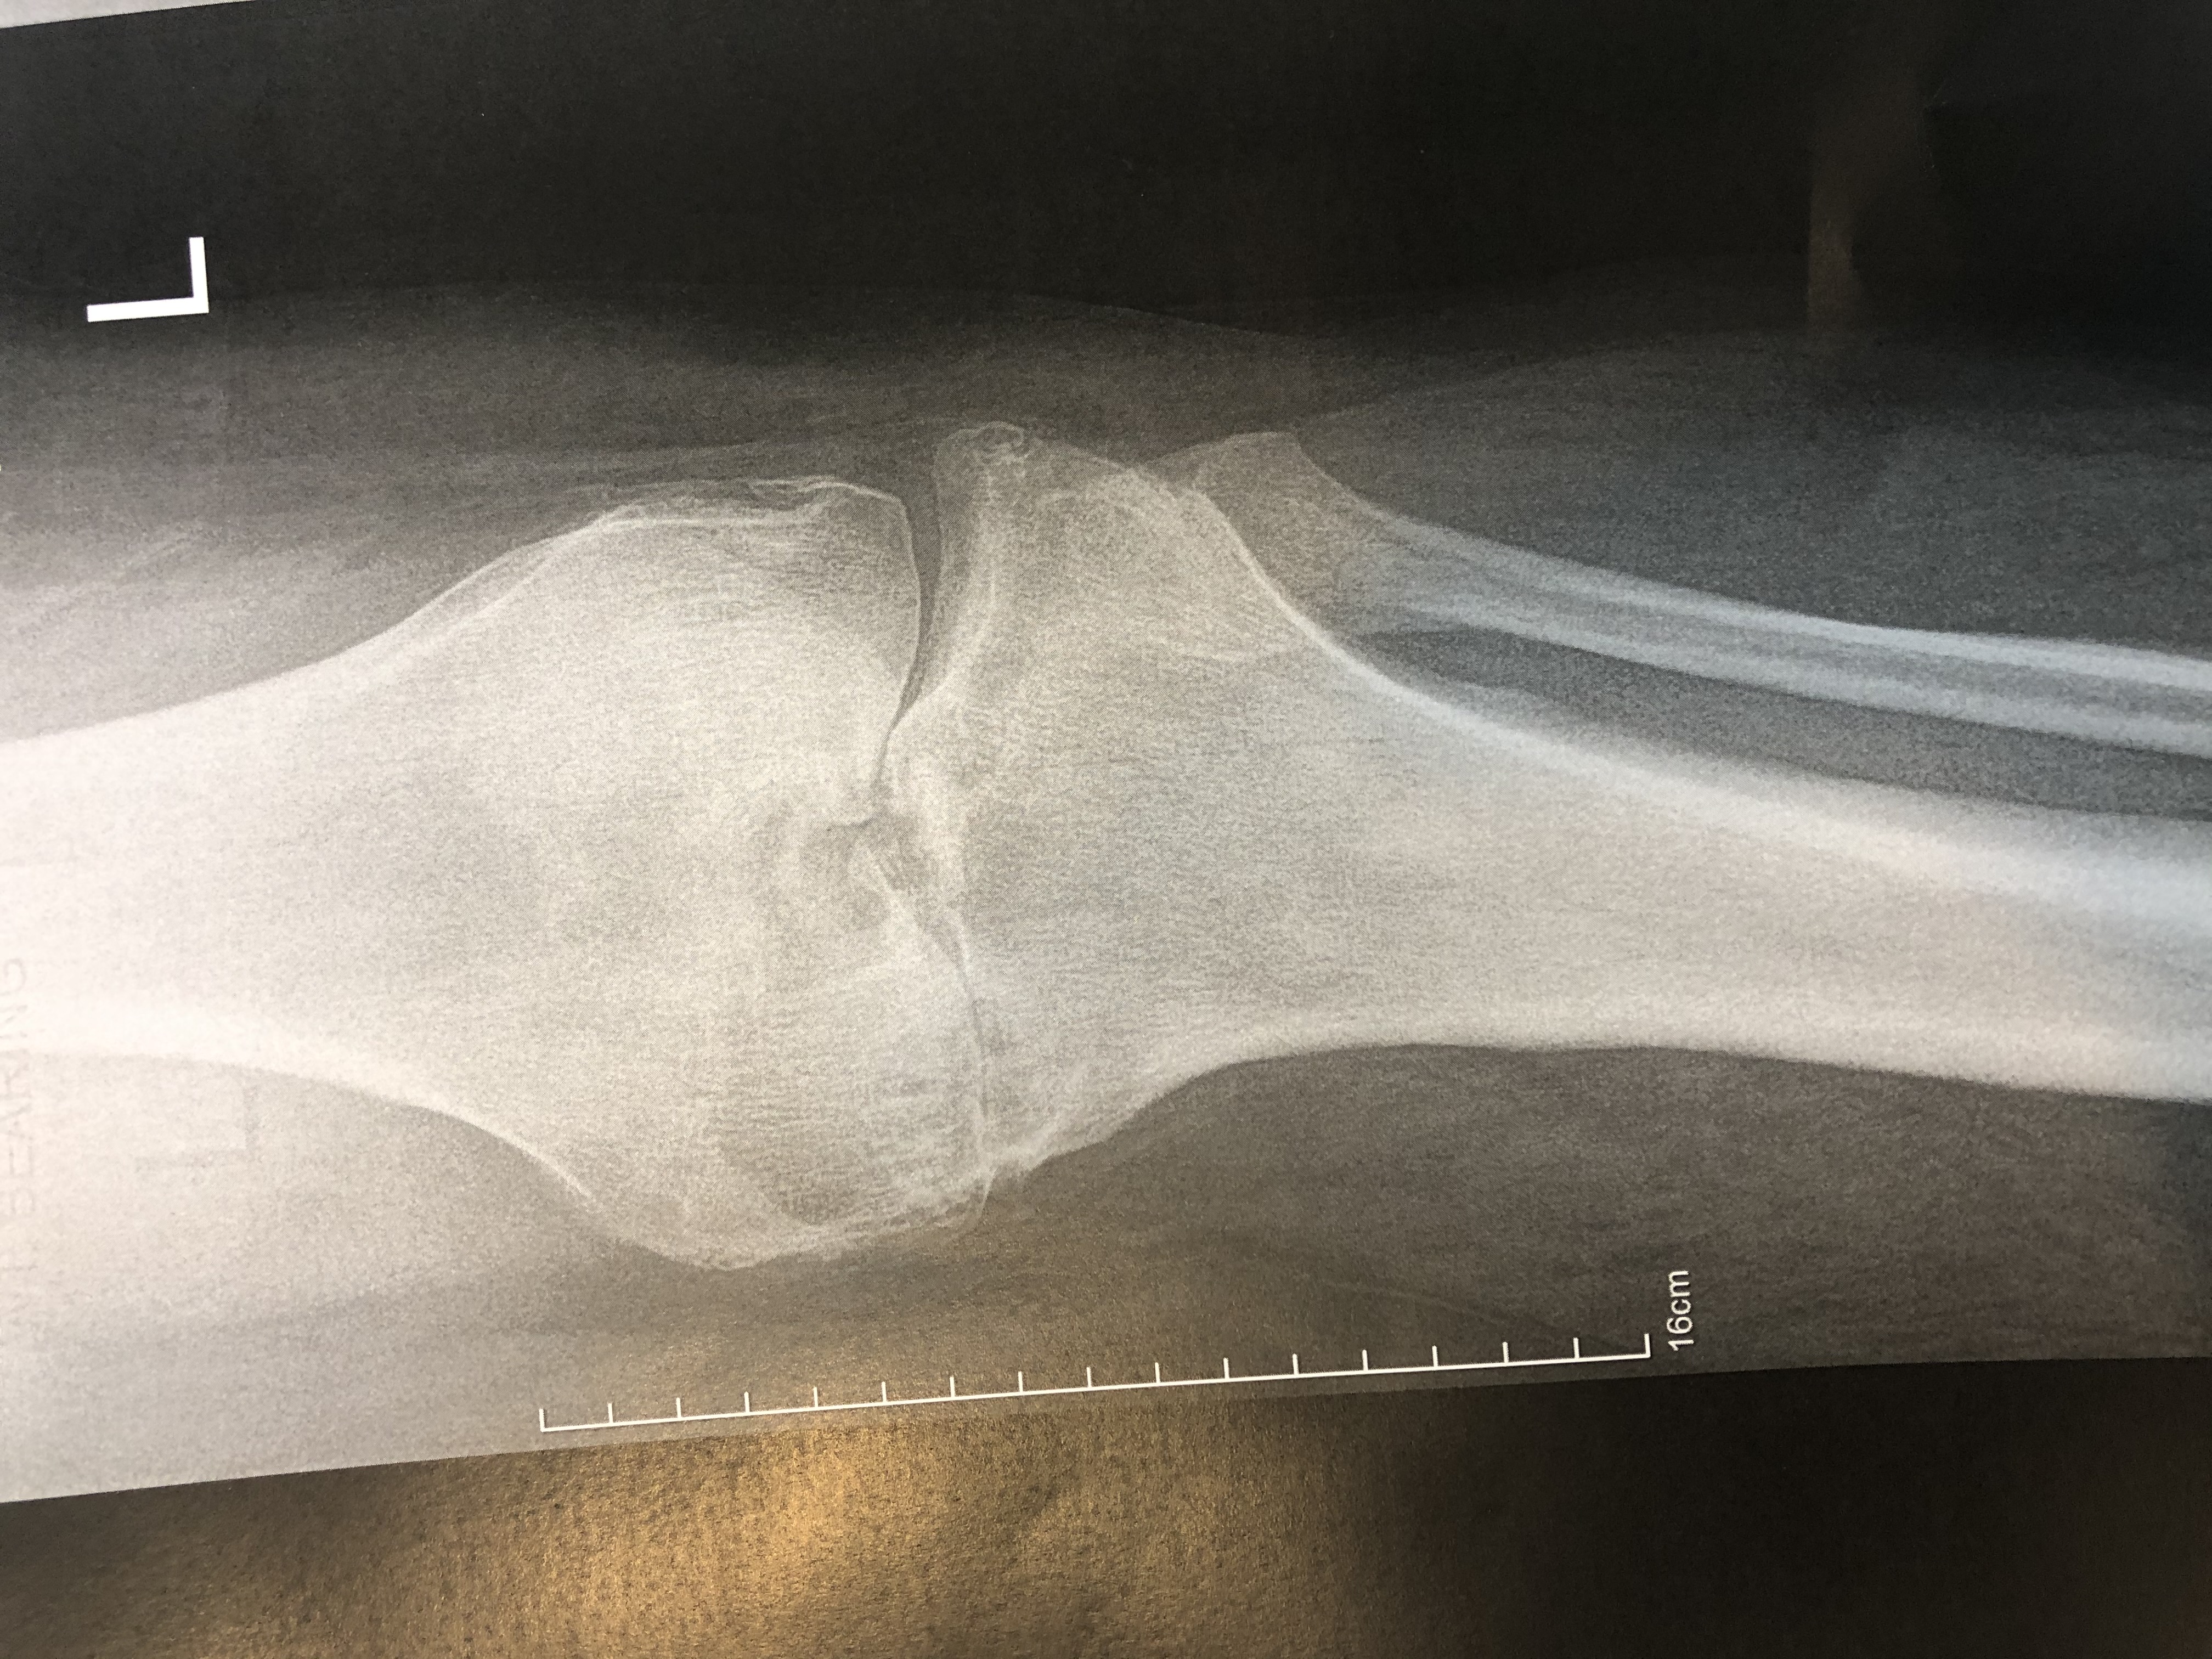

In knee OA, the protective cartilage that covers the ends of the bones within the knee joint gradually deteriorates, leading to friction, inflammation, and damage to the underlying bone. This results in pain, stiffness, swelling, and reduced range of motion in the affected knee. As the disease progresses, bone spurs (osteophytes) may develop, further contributing to joint pain and dysfunction.

The diagnosis of knee OA is typically based on a combination of clinical evaluation, medical history, physical examination findings, and imaging studies such as X-rays or MRI scans.